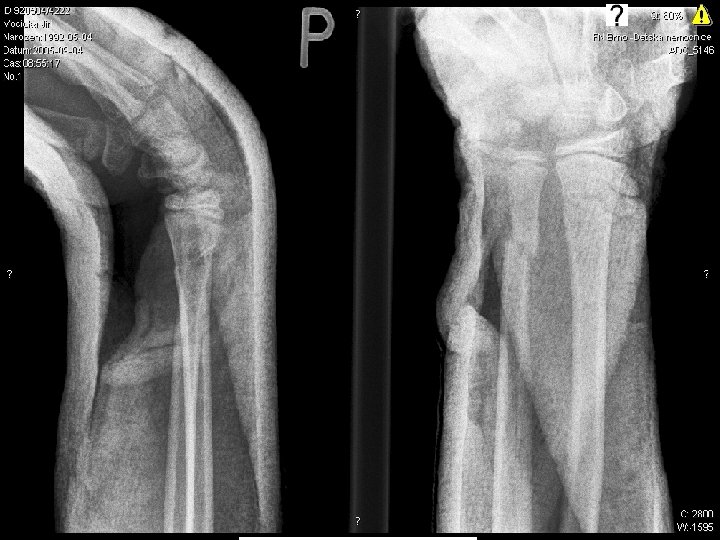

1

2

3

4

5

6

7

8

9

10 17. 4. 2005

Radiodiagnostic test conclusions

10